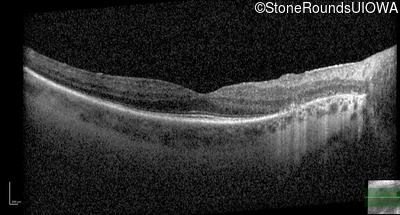

Optical Coherence Tomography - Left - 20/32 -1

Exemplar / OCT Stack

OCT Stack